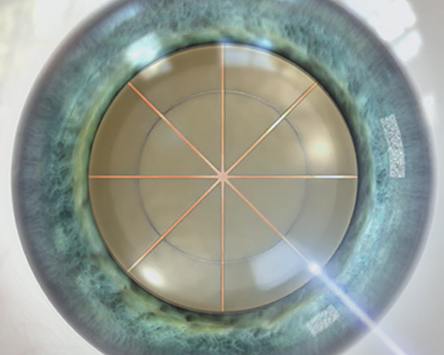

수정체 파쇄

부작용 확률을 낮추고, 수술 성공률을 높이기 위해

수정체 혼탁부위 파쇄시 정교한 파쇄가 필요합니다.

올레이저 노안백내장

균일하고 정교한

레이저 파쇄